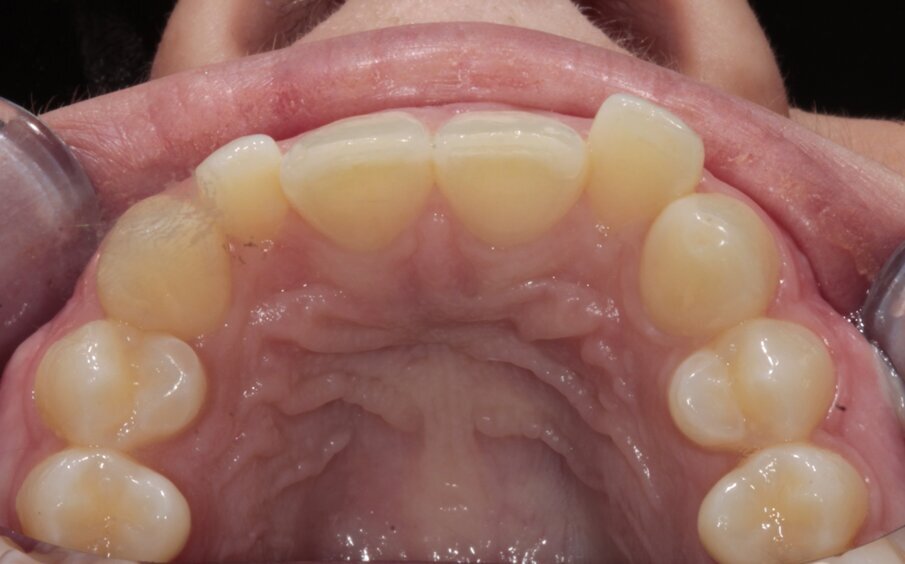

7. Initiële situatie, occlusaal

Tijdens het consult bleek dat de frontelementen in haar bovenkaak licht gebogen stonden en dat er wat chipping had plaatsgevonden aan de incisale randen. De onderste frontelementen vertoonden een lichte slijtage en zorgden door een functieprobleem ook voor de chipping aan de bovenste frontelementen. Alle orthodontische behandelingen werden besproken, waaronder een verwijzing naar een specialist. Een alternatieve behandeling werd aangeboden in de vorm van vaste aligners, clear aligners en Inman Aligners.

De patiënt besloot dat ze geen uitgebreide behandeling wilde en koos voor een behandeling van alleen de frontelementen met een uitneembare aligner, in dit geval de nieuwe Super Slim Inman Aligner. Ze wilde hiermee grote preparaties aan haar elementen voorkomen zodat ze naderhand alsnog veneers kon laten plaatsen. De Super Slim Aligner waarvoor werd gekozen, heeft een doorzichtige boog die nog dunner is dan het vorige design. Dit zorgt ervoor dat de lipaansluiting en spraak nog eenvoudiger wordt. Digitale behandelplanning werd gebruikt om de stand van de centrale incisieven naar voren te brengen en de laterale elementen juist naar achter te bewegen. Met digitale software (Spacewize™) kon worden beoordeeld of er genoeg ruimte was om later de retainerdraad met composiet te bevestigen en de juiste occlusie te bereiken. De digitale software zorgt er ook voor dat de behandelaar goed kan communiceren met het lab en zo controle houdt over de occlusie.

De bovenste frontelementen vertoonden exact 1mm crowding; interproximale reductie werd verdeeld over drie afspraken uitgevoerd met strips. De patiënt kreeg de Super Slim Aligner aangemeten om 18 uur per dag te dragen gedurende tien weken. De onderste elementen werden daarbij behandeld met een enkele Inman Aligner.